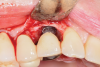

As in the first case, a composite allograft was placed into the defect that contained cryopreserved demineralized freeze-dried bone fibers with cancellous bone chips containing mesenchymal stem cells (Figure 14). This was layered with an amnion-chorion membrane. The flaps were repositioned and secured with 5-0 PTFE sutures using an interrupted technique.

Fig 14. A graft consisting of demineralized freeze-dried fibers and cryopreserved mineralized bone with stem cells was placed at the site. The graft was layered with an amnion-chorion membrane prior to flap closure.

Figure 14